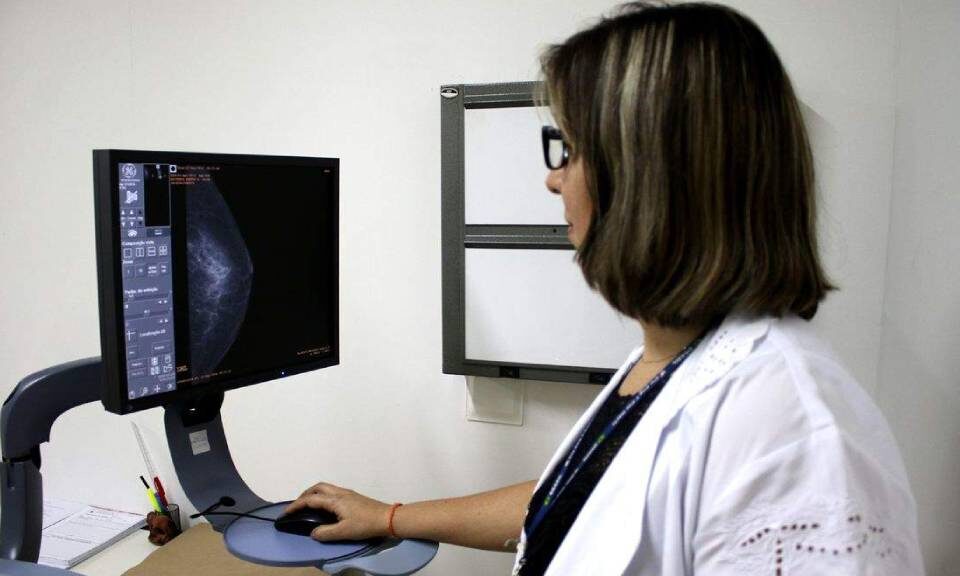

Em outubro, mês da campanha 'Outubro Rosa' de conscientização sobre o câncer de mama, o Espírito Santo comemora a ampliação do acesso à mamografia, que agora estará disponível para todas as mulheres a partir dos 40 anos.

Em outubro, a Prefeitura de Aracruz, por meio da Secretaria de Saúde, intensifica ações de prevenção ao câncer de mama e colo do útero. As Unidades Básicas de Saúde estão com horário estendido para orientar sobre mamografias e exames preventivos, visando informar e conscientizar mulheres de todas as idades.

A Assembleia Legislativa (Ales) promoveu, na manhã de quinta-feira (10), uma ação em apoio ao Outubro Rosa, com alunos de Enfermagem do Instituto Humboldt orientando servidoras e visitantes sobre prevenção ao câncer de mama e colo do útero, sob a supervisão da enfermeira Michelle Rocha.

Outubro é o mês do "Outubro Rosa", uma campanha global da OMS para conscientização sobre o câncer de mama. A Secretaria da Saúde destaca a importância do cuidado com a saúde da mulher, enfatizando a prevenção e a detecção precoce da doença, que afeta milhões de mulheres no Brasil e no mundo.